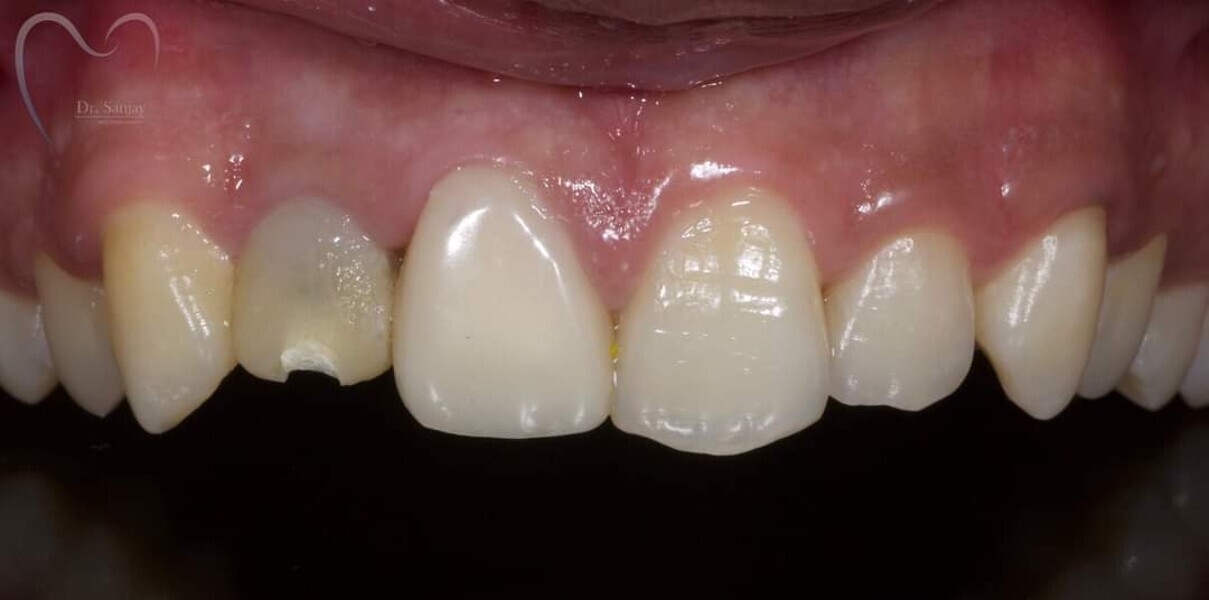

Esthetic Rehabilitation of Maxillary Anterior Teeth: Dr Sanjay Sah